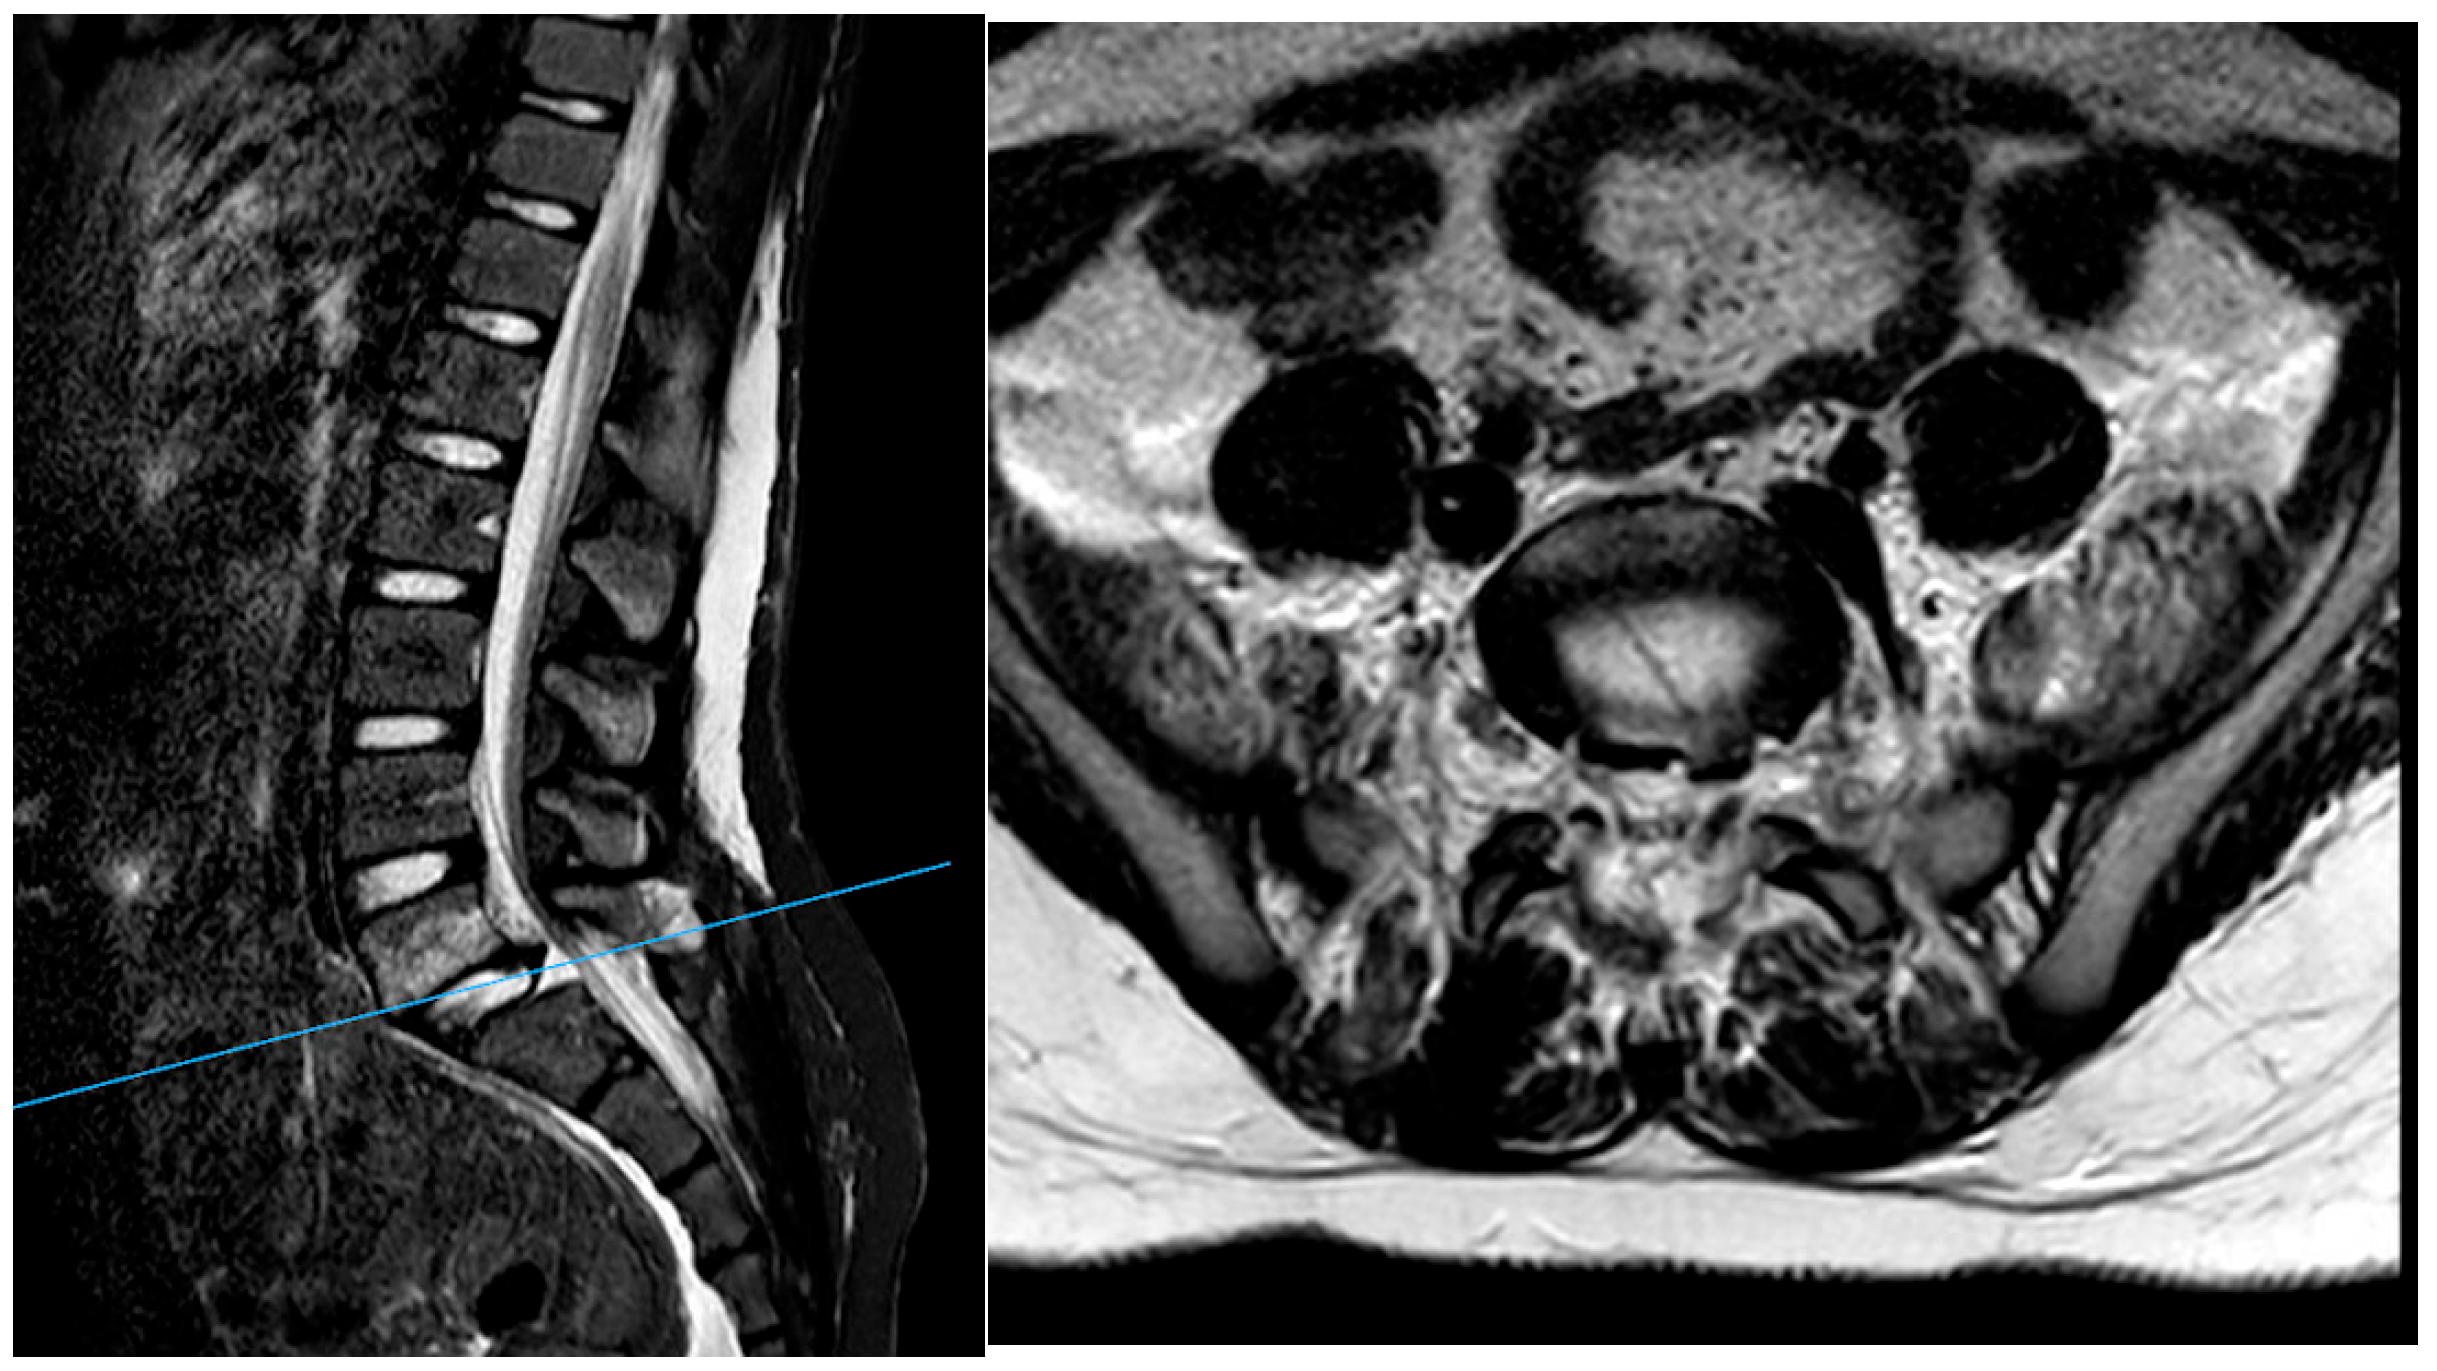

3. Case Report